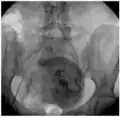

Перифиброидное сплетение при ЭМА.